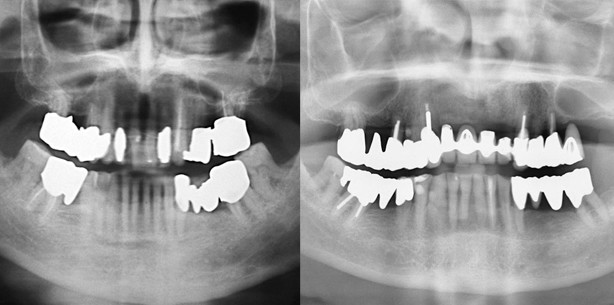

Der 59-jährige Patient suchte 1985 zur parodontalen Vorbehandlung vor prothetischer Neuversorgung die Abteilung für Parodontologie des Universitätsklinikums in Kiel auf. Der Patient war zeitlebens Nichtraucher und die Allgemeinanamnese war unauffällig. Intraoral zeigte sich ein prothetisch insuffizient versorgtes Gebiss (ZE ca. 15 Jahre in situ) mit weichen und harten Belägen (PI: 77 %). Die Gingiva war lokal livide gerötet und ödematös geschwollen, mit lokalisierten Rezessionen und Retraktionen der interdentalen Papillen (Abb. 1a). Ferner fanden sich sowohl zervikale kariöse Läsionen an 17, 14, 27, 37 und 47 (Abb. 1b) bzw. Sekundärkaries an den überstehenden Kronenrändern 13, 21, 23 als auch okklusale kariöse Läsionen an den Zähnen 24, 38 und 48. Die generalisierten Sondierungstiefen (ST) lagen zwischen 4 und 6 mm (Abb. 2). Alle Zähne, mit Ausnahme von 17, 15, 14, 37, 47 (Grad I) sowie 27 (Grad II) zeigten keine erhöhte Beweglichkeit (Lindhe und Nyman 1977). Die horizontale Sondierung der Furkationen ergab Grad I an 17, 14, 37, 47 und Grad II an 27 (Hamp et al. 1975). Die Panoramaschichtaufnahme (Abb. 3) zeigte einen generalisierten horizontalen Knochenabbau von circa einem Viertel, im Bereich der Unterkieferfront bis zur Hälfte der Wurzellänge. Weiterhin waren röntgenologische Aufhellungen in der Furkation 27, Verschattungen im Sinne überstehender Kronenränder an 17, 24, 37 und 47 sowie Verschattungen im Sinne von Wurzelfüllungen an 15, 23, 27 und 47 jeweils ohne periapikale Aufhellungen zu erkennen.

Die UPT umfasst bisher 27 Jahre und erfolgte regelmäßig in sechsmonatigem Intervall. Bei persistierenden ST 4 mm und Bluten auf Sondieren (BOP) sowie bei ST 5 mm erfolgte eine subgingivale Reinstrumentierung in der jeweiligen Sitzung. Bei einer Reevaluation 1990 wurde der Erhalt des Zahnes 38 als nicht sinnvoll eingestuft und er wurde entfernt. Bis zu diesem Zeitpunkt war röntgenologisch kein progressiver Knochenabbau erkennbar (Abb. 4a–c). Die Wurzel des Zahnes 12 wurde 1994 infolge einer erfolglosen endodontischen Behandlung unter der verblockten Rekonstruktion der Oberkieferfront entfernt (Abb. 5b, intraorale Ansicht 2005, elf Jahre nach Entfernung der Wurzel 12). Im Jahr 2010 wurde der Zahn 21 nach einer fehlgeschlagenen endodontischen Behandlung (alio loco) und einer Perforation der Wurzel im mittleren Wurzeldrittel ebenfalls unter der bestehenden verblockten Krone entfernt. Ebenso musste die Wurzel des Zahnes 22 im Jahr 2012 aufgrund einer Längsfraktur unter Erhalt der bestehenden prothetischen Versorgung entfernt werden (Abb. 5c, intraorale Ansicht 2012, nach Entfernung der Wurzeln 21, 22 und 12). Bei einer Reevaluation 2012 zeigte die Panoramaschichtaufnahme gegenüber dem Ausgangsbefund keinen klinisch relevanten weiteren Knochenabbau.